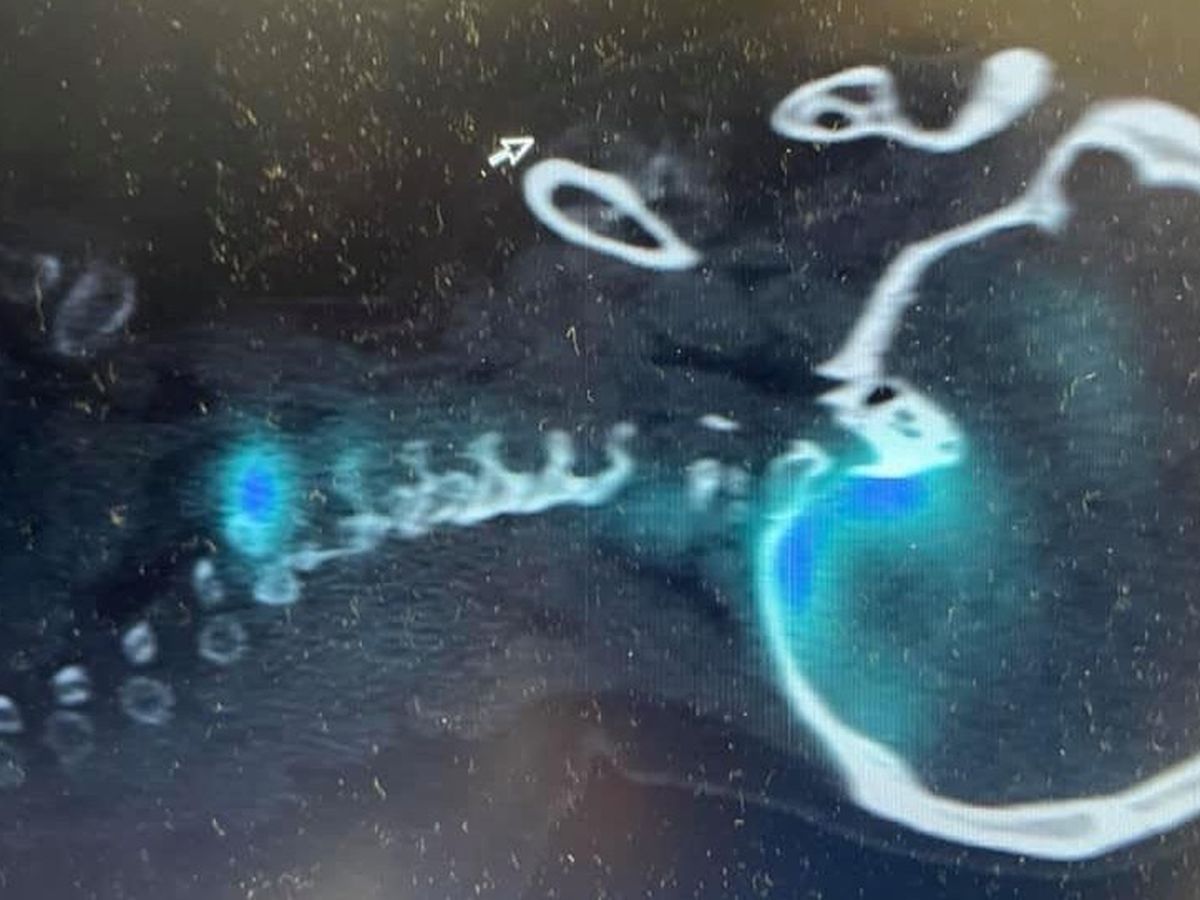

Later discovering she had a spontaneous spinal fluid leak resulting in a sagging brain, it was evident that Heather’s recovery was going to be more long term than expected. Spending several weeks in hospital, away from her younger boys and with Steve by her side providing the extra support needed when talking to doctors ect. treatment of a blood patch was administered just before Easter. Movement would be further restricted for a number of weeks to allow the blood patch to heal.

Unfortunately they have suffered another blow recently when their eldest son Morgan, came off his bike, causing damage to the right eye socket and left frontal lobe. At one point in this journey Morgan and Heather were both in hospital and Steve was right there with them the entire time, moving between wards checking in on them both.

Thankfully Morgans prognosis is positive but as you can imagine with any sort of brain injury, just like his mum, recovery will be long term. It’s been a rocky few weeks as we’ve watched his short term memory bounce all over the place. On a recent visit to his hospital bed, Morgan didn’t remember my name, although he spoke to me like he knew exactly who I was. As I write this, Townsville Hospital are arranging to have him sent to Brisbane for rehab. Steve, who has been there with him since the accident, will be traveling down to be with him, to keep him company and be available for any medical related questions and decision making.